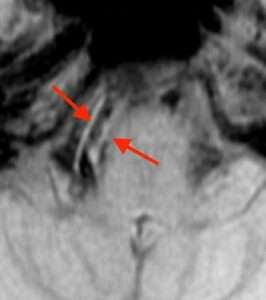

T1BB(T1 black blood)法とは、血管内にできた不安定でくずれやすい血栓(血液の固まり)を描き出す技術です。

このように、血管の壁に沿って白く見える部分が不安定な血栓を表しています。すでに古くなって固まった血栓は写らないので、新たに生じた血栓が分かります3) 4) 5) 。